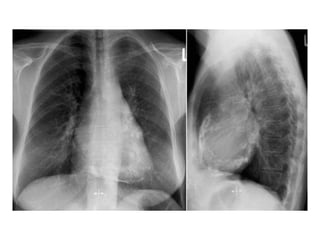

   The cardiac silhouette can be enlarged secondary to a coexisting pericardial

effusion.

   Pericardial calcification is seen in a minority of patients and should raise the

suspicion of tuberculous pericarditis, but calcification per se is not diagnostic of

constrictive physiology.

   The lateral chest film is useful to detect pericardial calcification along the right

heart border and in the atrioventricular groove.

   Isolated calcification of the LV apex or posterior wall suggests ventricular

aneurysm rather than pericardial calcification.

   Pleural effusions are occasionally noted and can be a presenting sign of

constrictive pericarditis.

   When left heart filling pressures are markedly elevated, pulmonary vascular

congestion and redistribution can be present.

Chest radiograph showing marked pericardial calcifications

in a patient with constrictive pericarditis.